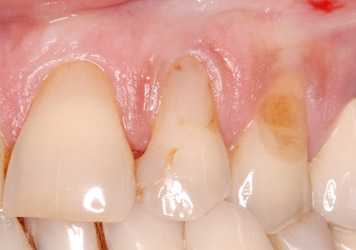

L’incisive centrale droite est mobile et disgracieuse. Les dents voisines du patient sont colorées et porteuses d’anciennes résines.

L’incisive latérale droite est porteuse d’un kyste important. Une maladie parodontale chronique généralisée génère des mobilités dentaires et des saignements gingivaux.

Le traitement parodontal non chirurgical a stabilisé la maladie parodontale et a permis la pose de deux implants en sites de deux incisives et de facettes sur les dents voisines.

Le patient a retrouvé l’esthétique de son sourire et le confort.